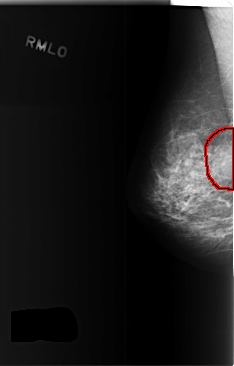

C_0372_1.RIGHT_MLO

RIGHT_MLO LINES 5856 PIXELS_PER_LINE 3736 BITS_PER_PIXEL 12 RESOLUTION 50 OVERLAY

FILE: C_0372_1.RIGHT_MLO.OVERLAY

TOTAL_ABNORMALITIES 1

ABNORMALITY 1

LESION_TYPE MASS SHAPE OVAL MARGINS OBSCURED

ASSESSMENT 3

SUBTLETY 4

PATHOLOGY BENIGN

TOTAL_OUTLINES 1

BOUNDARY